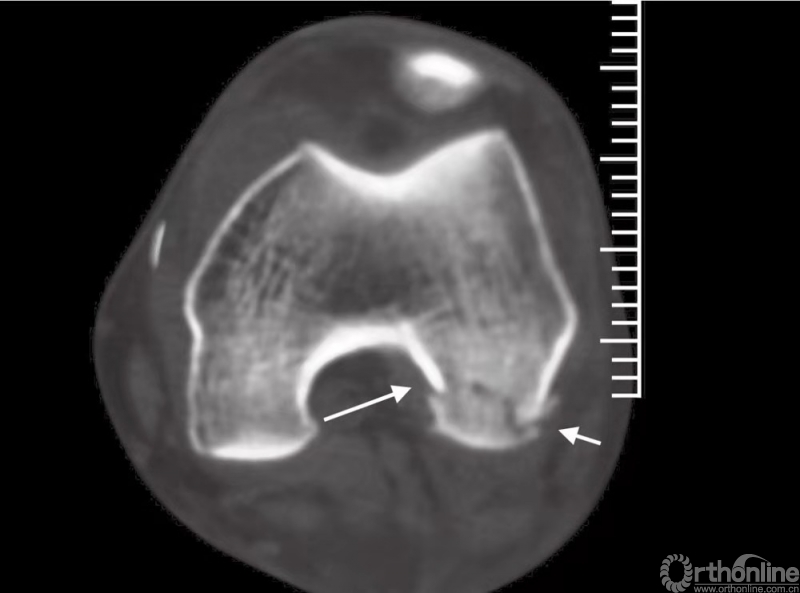

因此,不正确的正常膝关节视图将会给我们留下错误的印象,斜位片也可以帮助显示,因而,CT检查是必要的(图1)。而磁共振成像(MRI)会有助于评估膝关节周围软组织(例如韧带或半月板)损伤情况。

图1 CT显示患者存在LetenneurⅡC型股骨外侧髁Hoffa骨折